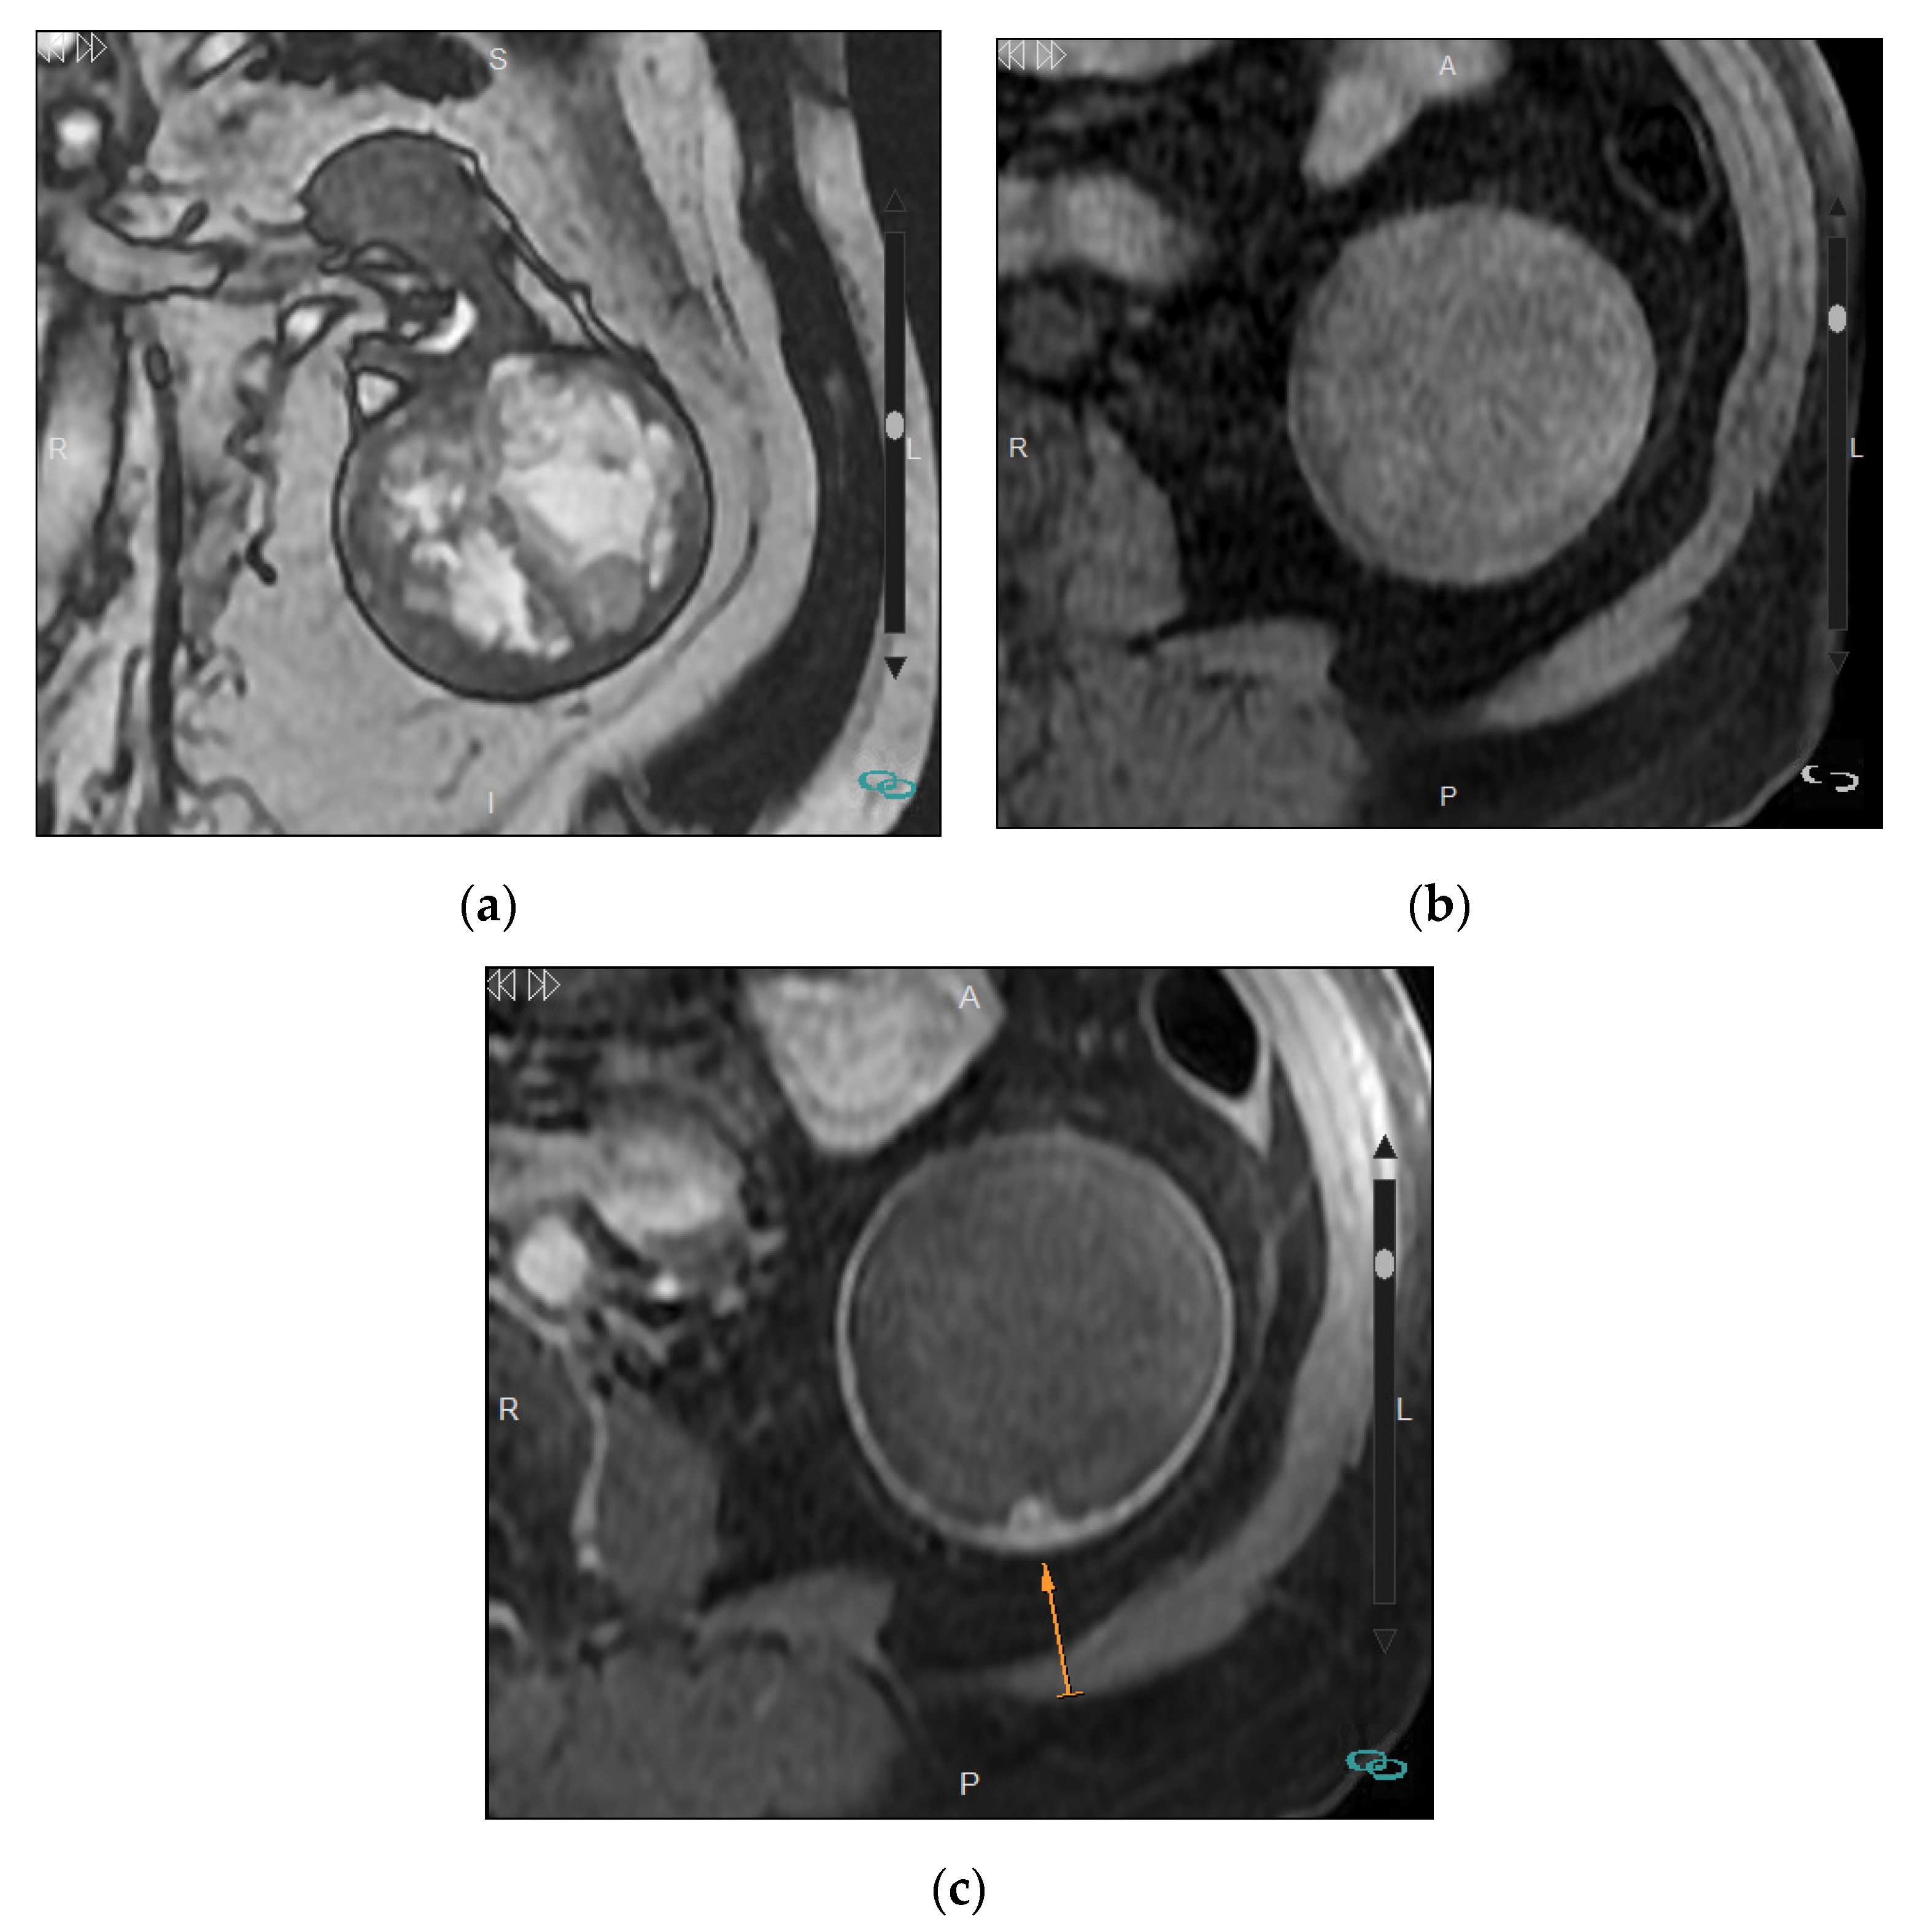

3. Characterization of Cystic Masses

Bosniak Classification